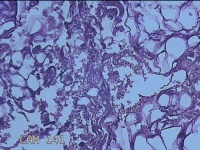

外阴部包块

性别

女

年龄

37岁

临床诊断

皮脂腺囊肿

一般病史

外阴部起包块一月余。

标本名称

大体所见

灰白暗红色包块2.3x1.8x0.8cm一个,表面糜烂,切开包块呈实性,切面灰白淡黄色,质软。

有那么点像脂肪瘤。